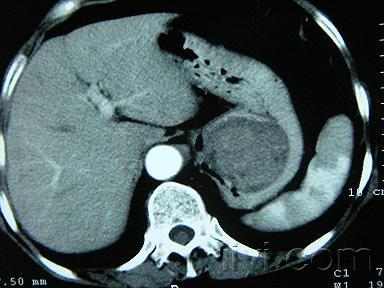

術(shù)前通常難以確診。胃鏡檢查可見隆起于胃黏膜下的半球形腫塊。胃腸氣鋇造影可見邊緣規(guī)則的充盈缺損,腫瘤表面胃黏膜光滑。B超和CT檢查多可確定腫瘤的位置、大小以及與周圍臟器的關(guān)系。